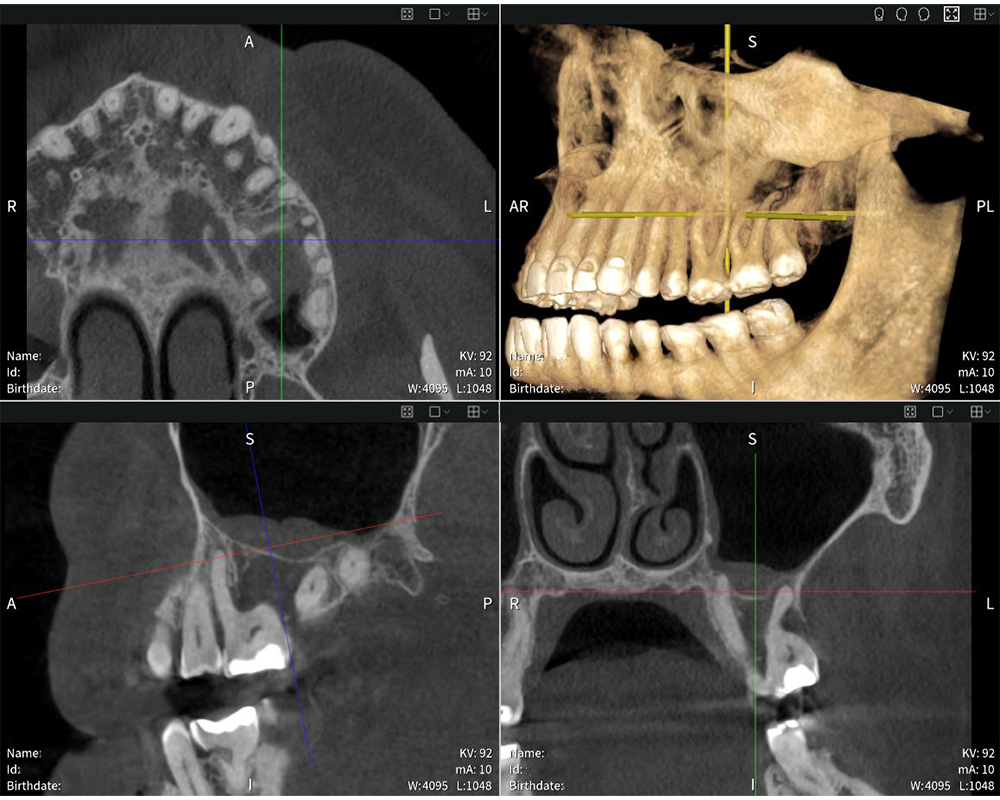

Seethrough Max sienta nuevas bases en términos de intuitividad. Su diseño abierto y sus generosas dimensiones ofrecen una comodidad óptima para los pacientes y aseguran una aceptación especialmente alta. Además, la colocación cara a cara simplifica la comunicación entre el usuario y el paciente. «La colocación funciona de manera excelente. Valoro poder estar frente a los pacientes y mantener contacto visual con ellos. Eso me ayuda a determinar la posición óptima del paciente para lograr una imagen precisa», comenta el Dr. en odontología Mauro Amato. Como complemento al potente hardware, Seethrough Studio ofrece imágenes nítidas, detalladas y sin distorsiones. El avanzado algoritmo de corrección del movimiento mejora la calidad de imagen tanto en imágenes 3D como 2D. Con un campo de visión de hasta 17 × 17 cm, Seethrough Max cubre una amplia gama de aplicaciones, desde endodoncia e implantología hasta cirugía oral y otorrinolaringología, con una dosis mínima de radiación. «Las radiografías sorprenden por su extraordinaria nitidez y profundidad de detalle, lo que permite realizar un diagnóstico exacto y una planificación precisa del tratamiento», destaca el Dr. en odontología Mauro Amato.

Seethrough Max combina una estructura compacta con una calidad de imagen extraordinaria y no tiene nada que envidiarle a su homólogo más grande. Con la mejor relación del mercado entre campo de visión y dimensiones, Seethrough Flex ofrece una amplia cobertura de FOV de hasta 14 × 10 cm. Al igual que Seethrough Max, el equipo CBCT se beneficia del potente software Studio Seethrough, que optimiza la calidad de imagen y los flujos de trabajo digitales. «El software sorprende por su uso intuitivo. La interfaz de usuario es fácil de usar, lo que me permite acceder rápidamente a las herramientas y vistas que necesito», explica el Dr. en odontología Mauro Amato. Y añade: «El software me permite visualizar las imágenes en distintas perspectivas y encontrar las respuestas que necesito de forma rápida y eficaz». Los equipos Seethrough están conectados con ioDent® de forma predeterminada. La avanzada plataforma online de W&H combina datos importantes de los pacientes, una comunicación fluida y numerosos servicios útiles y de a poyo que hacen más eficiente el día a día de la clínica.